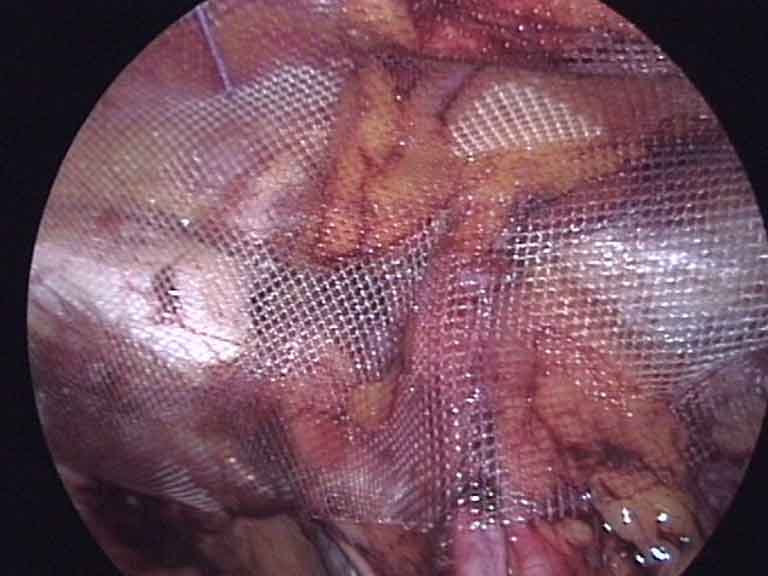

Laparoscopic view during abdominal wall hernia repair

Abdominal Wall Hernia

Laparoscopic Abdominal Wall Hernia Surgery

Keyhole repair of hernias in the abdominal wall — umbilical, ventral, incisional, and diaphragmatic hernias, as well as divarication of recti. A mesh is placed through small cuts to reinforce the abdominal wall without a large open wound.